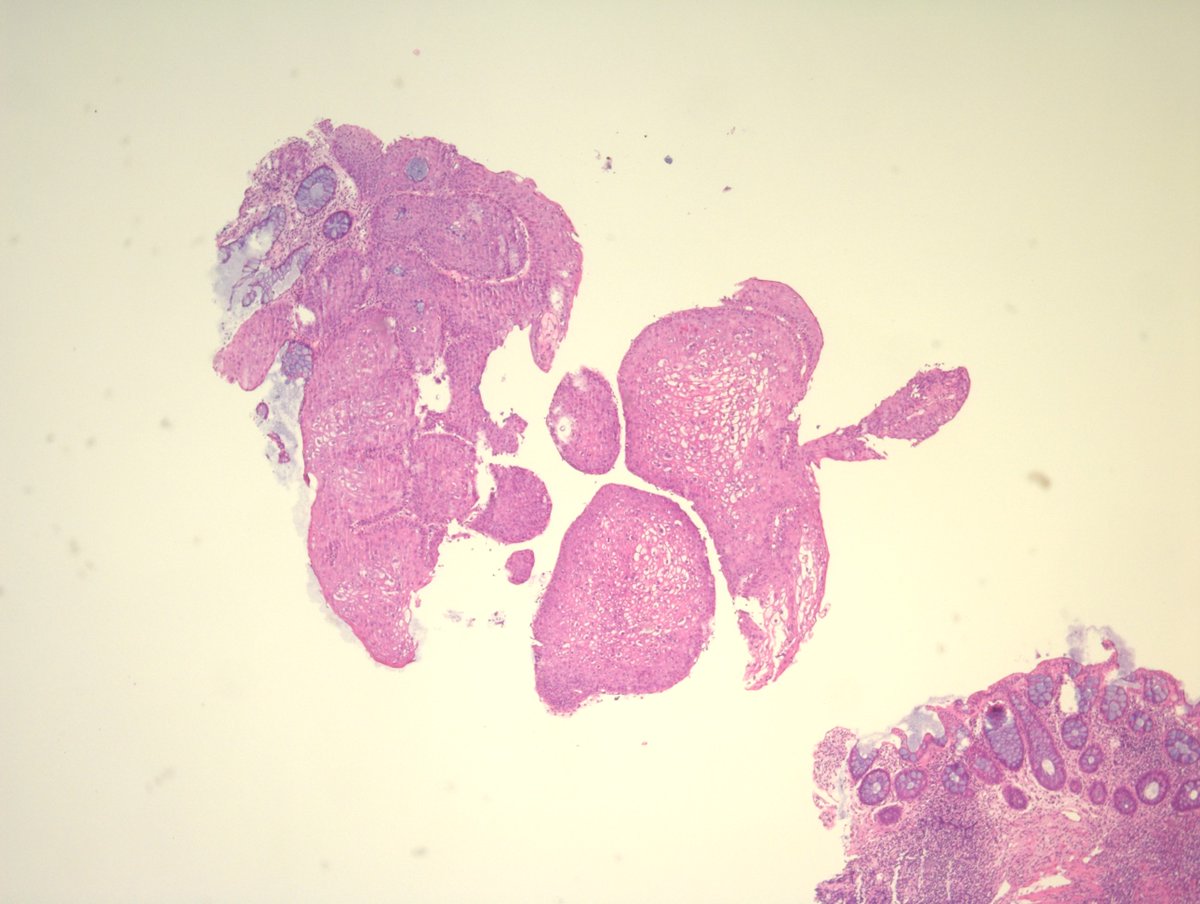

Cystic lung tissue from a 12-month-old. Diagnosis? A) Lymphangioleiomyomatosis B) Pleuropulmonary blastoma C) Pulmonary blastoma #pulmpath #pathresidents #pathresidents #pedipath

A) Lymphangioleiomyomatosis

B) Pleuropulmonary blastoma

C) Pulmonary blastoma